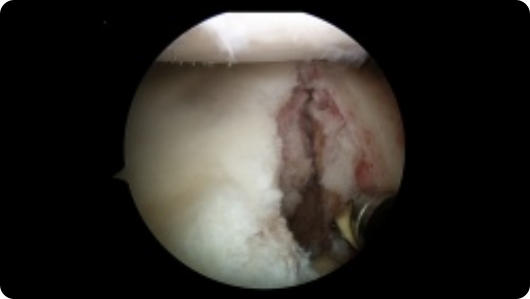

Arthroscopic image of an ACL tear Arthroscopic image of an ACL reconstruction

ACL Tear